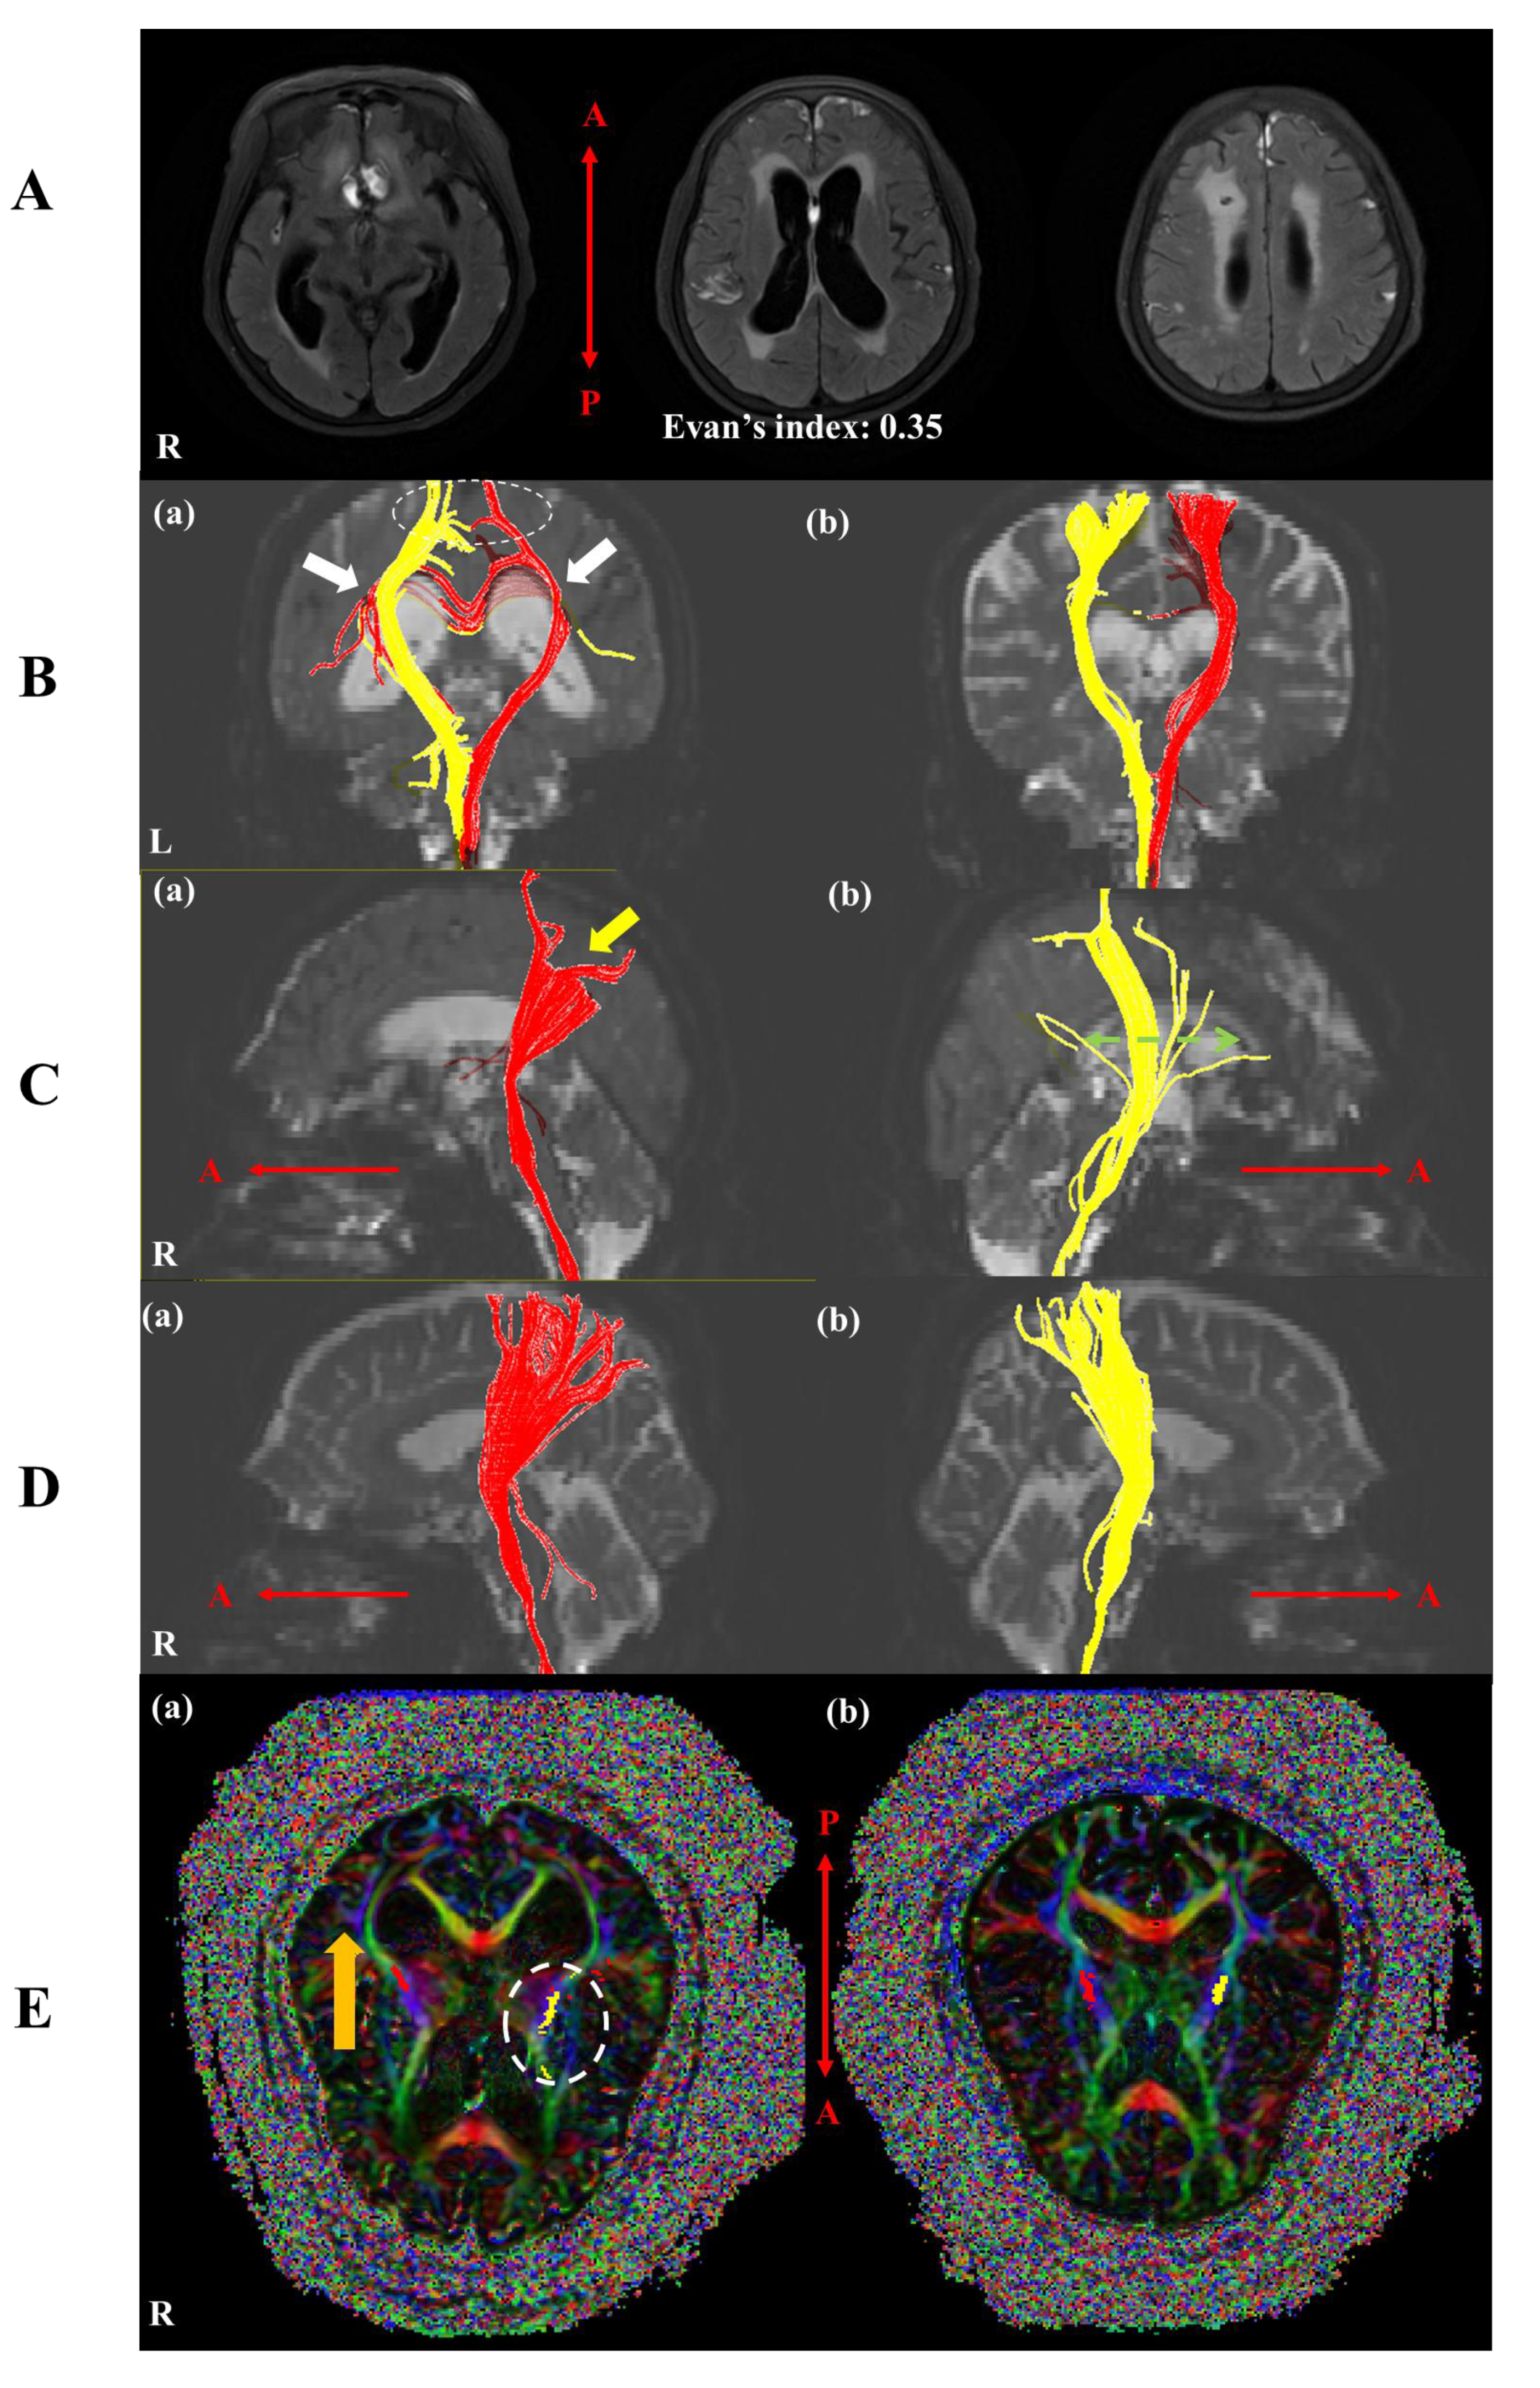

2. Case Presentation

3. Diffusion Tensor Imaging